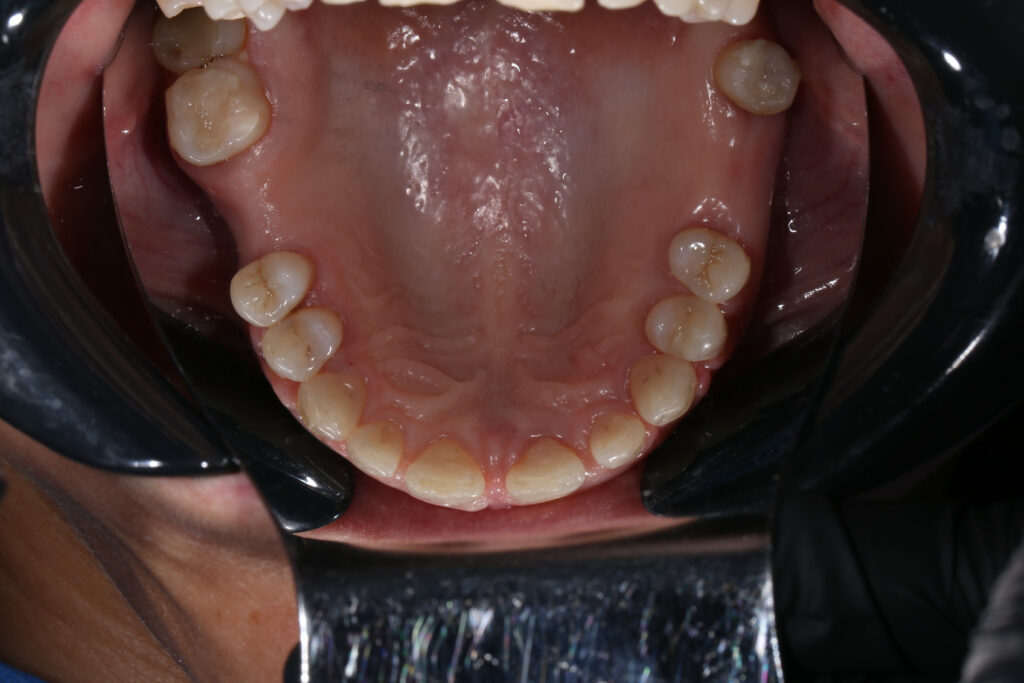

Ситуация до лечения

Пациентка 39 лет была направлена стоматологом-ортопедом для ортодонтической подготовки перед протезированием.

Из-за множественных давних удалений жевательных зубов, произошла деформация зубных рядов, зубы разъехались в область удаленных, что затрудняло протезирование в момент обращения к ортопеду.

Так же можно отметить сильное снижение высоты прикуса (верхние зубы на 100% перекрывали нижние, что вызывало хроническую травму десны), а также повышенную стираемость твердых тканей зубов,

что является следствием повышенной нагрузки, которую много лет испытывали передние зубы, в связи с отсутствием жевательных зубов.

пациент до брекетов